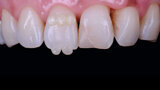

Jednoduchá souhra odstínů k vytvoření opticky harmonické výplně